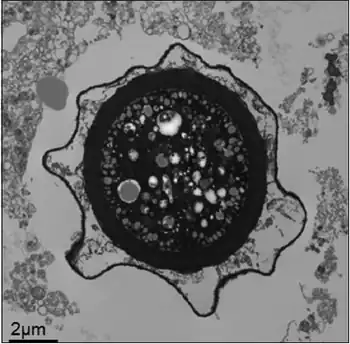

B. mandrillaris is a free-living, heterotrophic amoeba, consisting of a standard complement of organelles surrounded by a three-layered cell wall (thought to be made of cellulose), and with an abnormally large cell nucleus. On average, a Balamuthia trophozoite is about 30 to 120 μm in diameter. The cysts fall around this range, as well.[8]

Balamuthia's lifecycle, like the Acanthamoeba, consists of a cystic stage and a non-flagellated trophozoite stage, both of which are infectious, and both of which can be identified in the brain tissue on microscopic examination of brain biopsies performed on infected individuals. The trophozoite is pleomorphic and uninucleated, but binucleated forms are occasionally seen. Cysts are also uninucleated, possessing three walls: an outer thin irregular ectocyst, an inner thick endocyst, and a middle amorphous fibrillar mesocyst.[9]